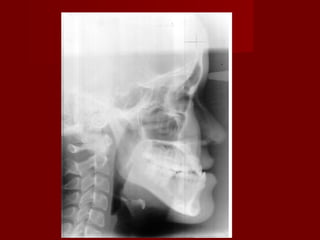

DiagnosisDiagnosis

– Differentiate skeletal from non-skeletalDifferentiate skeletal from non-skeletal

problemproblem

Examination ??Examination ??

 Profile viewProfile view

 Skeletal pattern I vs IIISkeletal pattern I vs III

Cephalometric analysis ??Cephalometric analysis ??

 ANB ??ANB ??

 Wits ??Wits ??

ANB -2 degree

AO-BO -3mm

Upper 1 to FHP _ 115

Lower 1 to MP _94

ANB -2 degree AO-BO-3mm Upper 1 to FHP _ 115 Lower 1 to MP _94